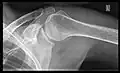

Shoulders

These include:

- AP-projection 40° posterior oblique after Grashey

The body has to be rotated about 30 to 45 degrees towards the shoulder to be imaged, and the standing or sitting patient lets the arm hang. This method reveals the joint gap and the vertical alignment towards the socket.[17]

In the UK, the standard projections of the shoulder are AP and Lateral Scapula or Axillary Projection.[15]

-

Transaxillary -

Y-projection